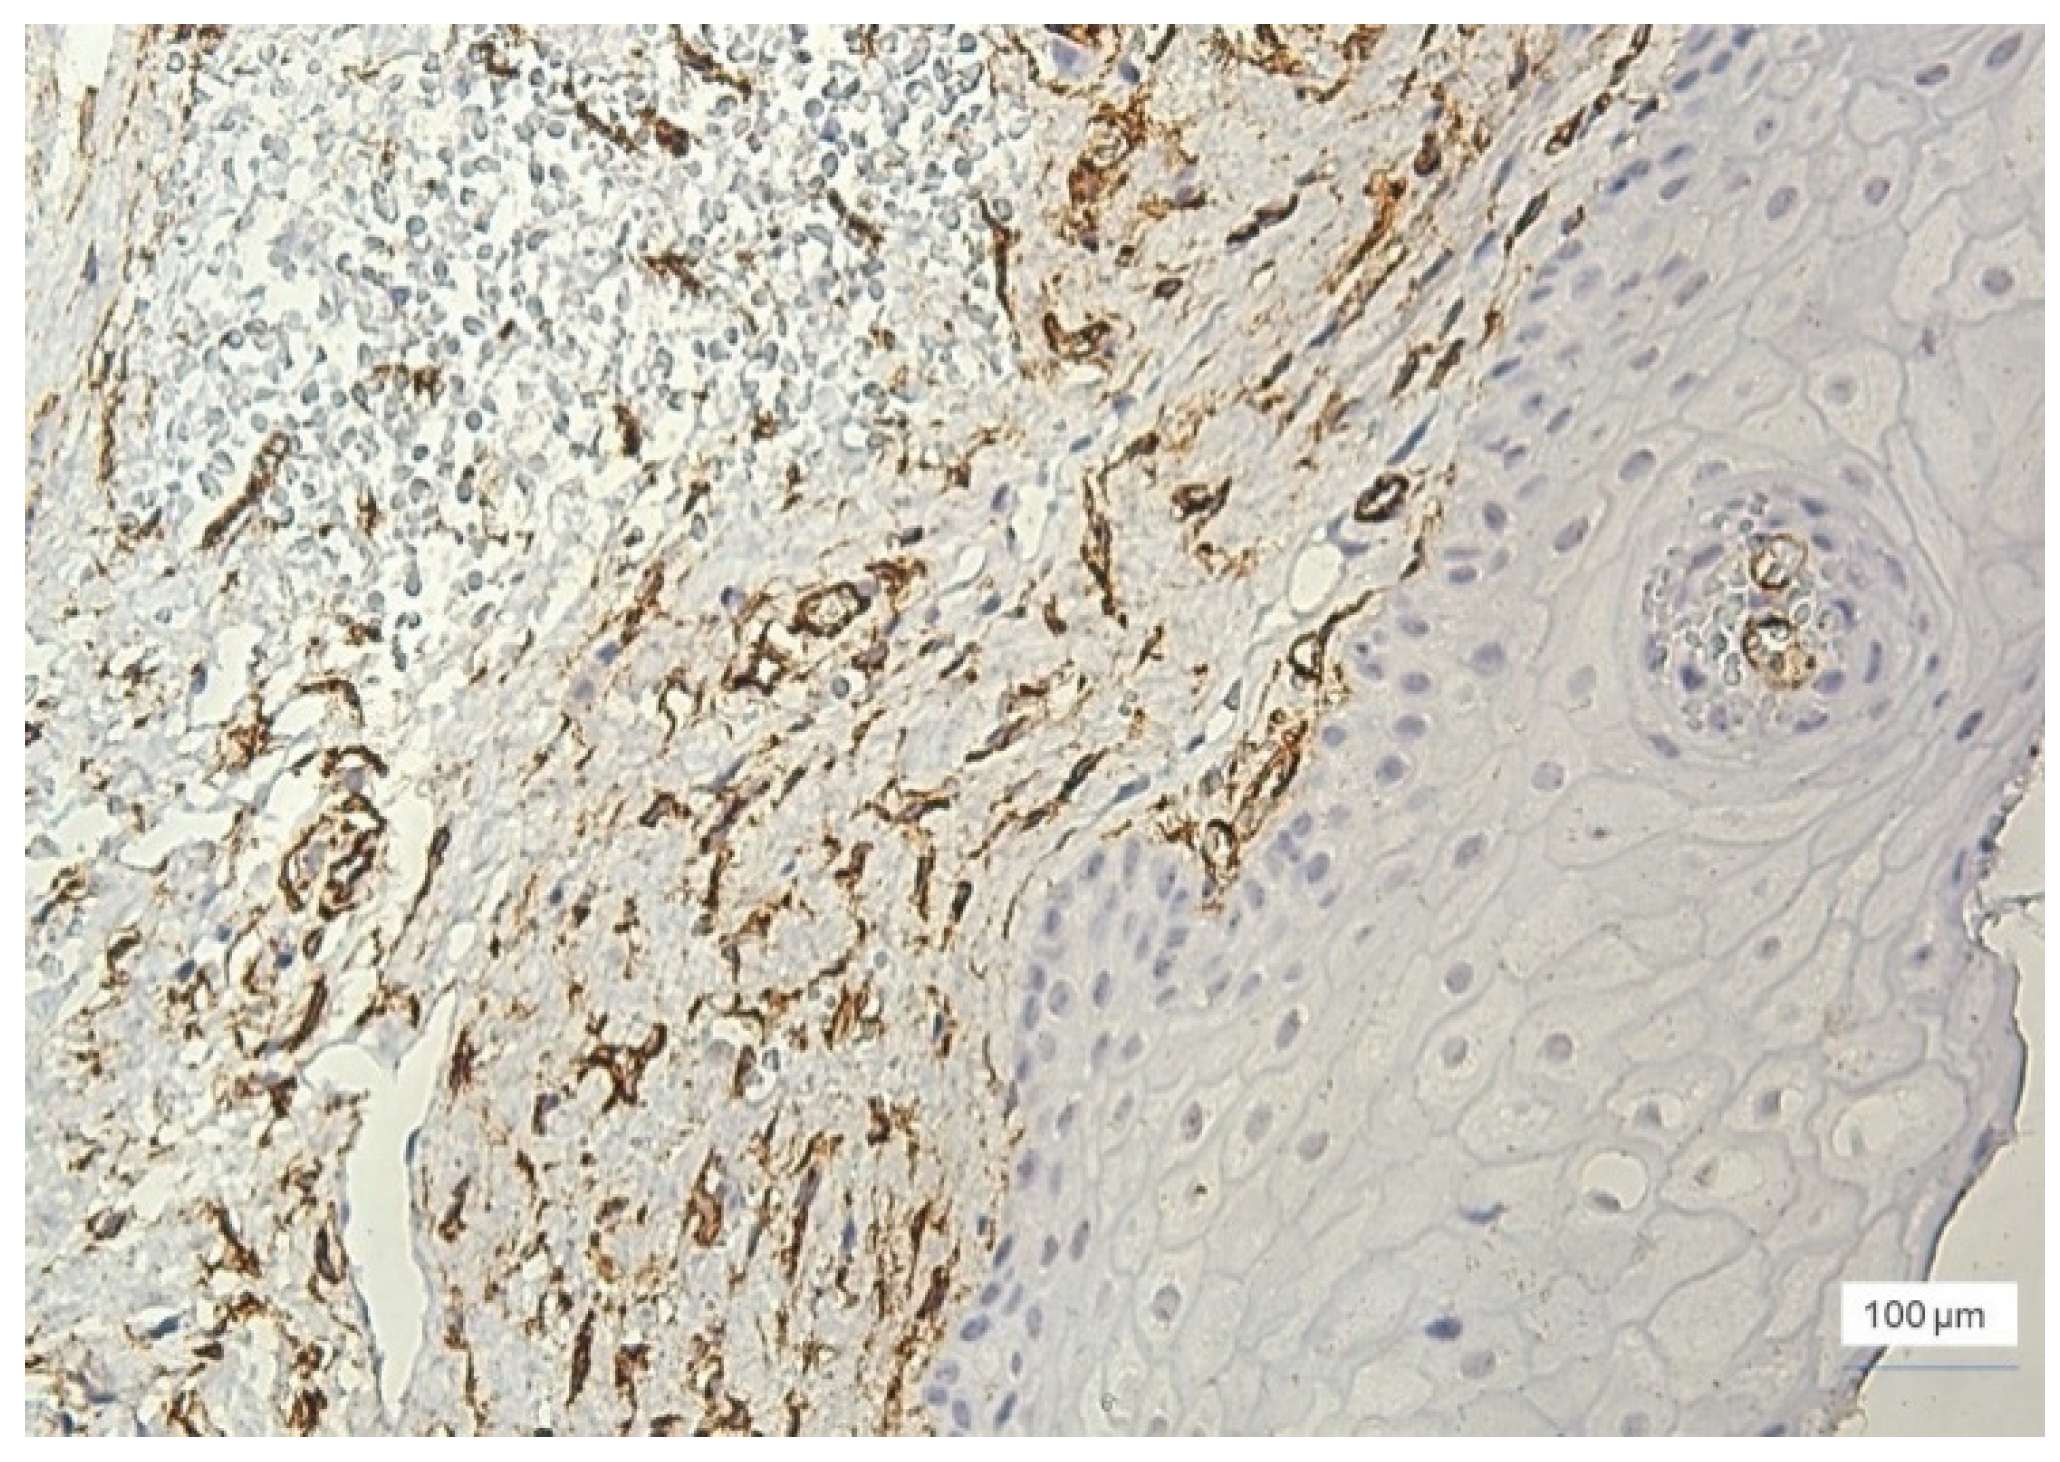

Most cases with severe inflammation showed extensive areas of bleeding. In these cases, we identified large dilated vessels with dilated stasis and numerous branches, suggesting the activation of endothelial cells (Figure 4).

As expected, the highest values for MVD were observed in cases of severe inflammation, where the total number of vessels was between 35–89/field, most of them being observed in the stroma (Figure 7). Two cases with severe inflammation showed a lower MVD (20–25 vessels/field).

Figure 7. Severe inflammation, GI = 3, increased microvessel density at the stromal level, vascular polymorphism, anti-CD34 immunohistochemical staining, and DAB chromogen, ×100.